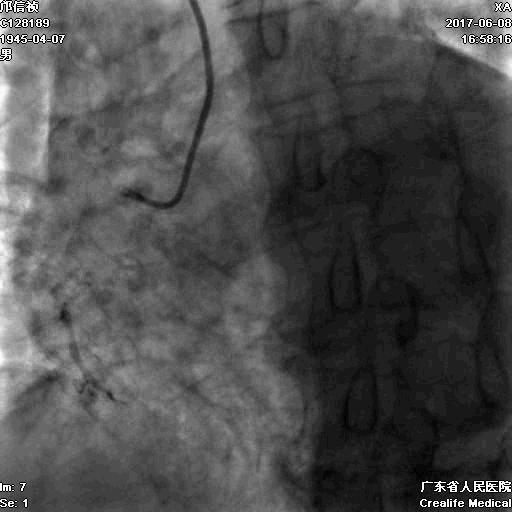

RCA闭塞段球囊扩张后IVUS

支架术后IVUS